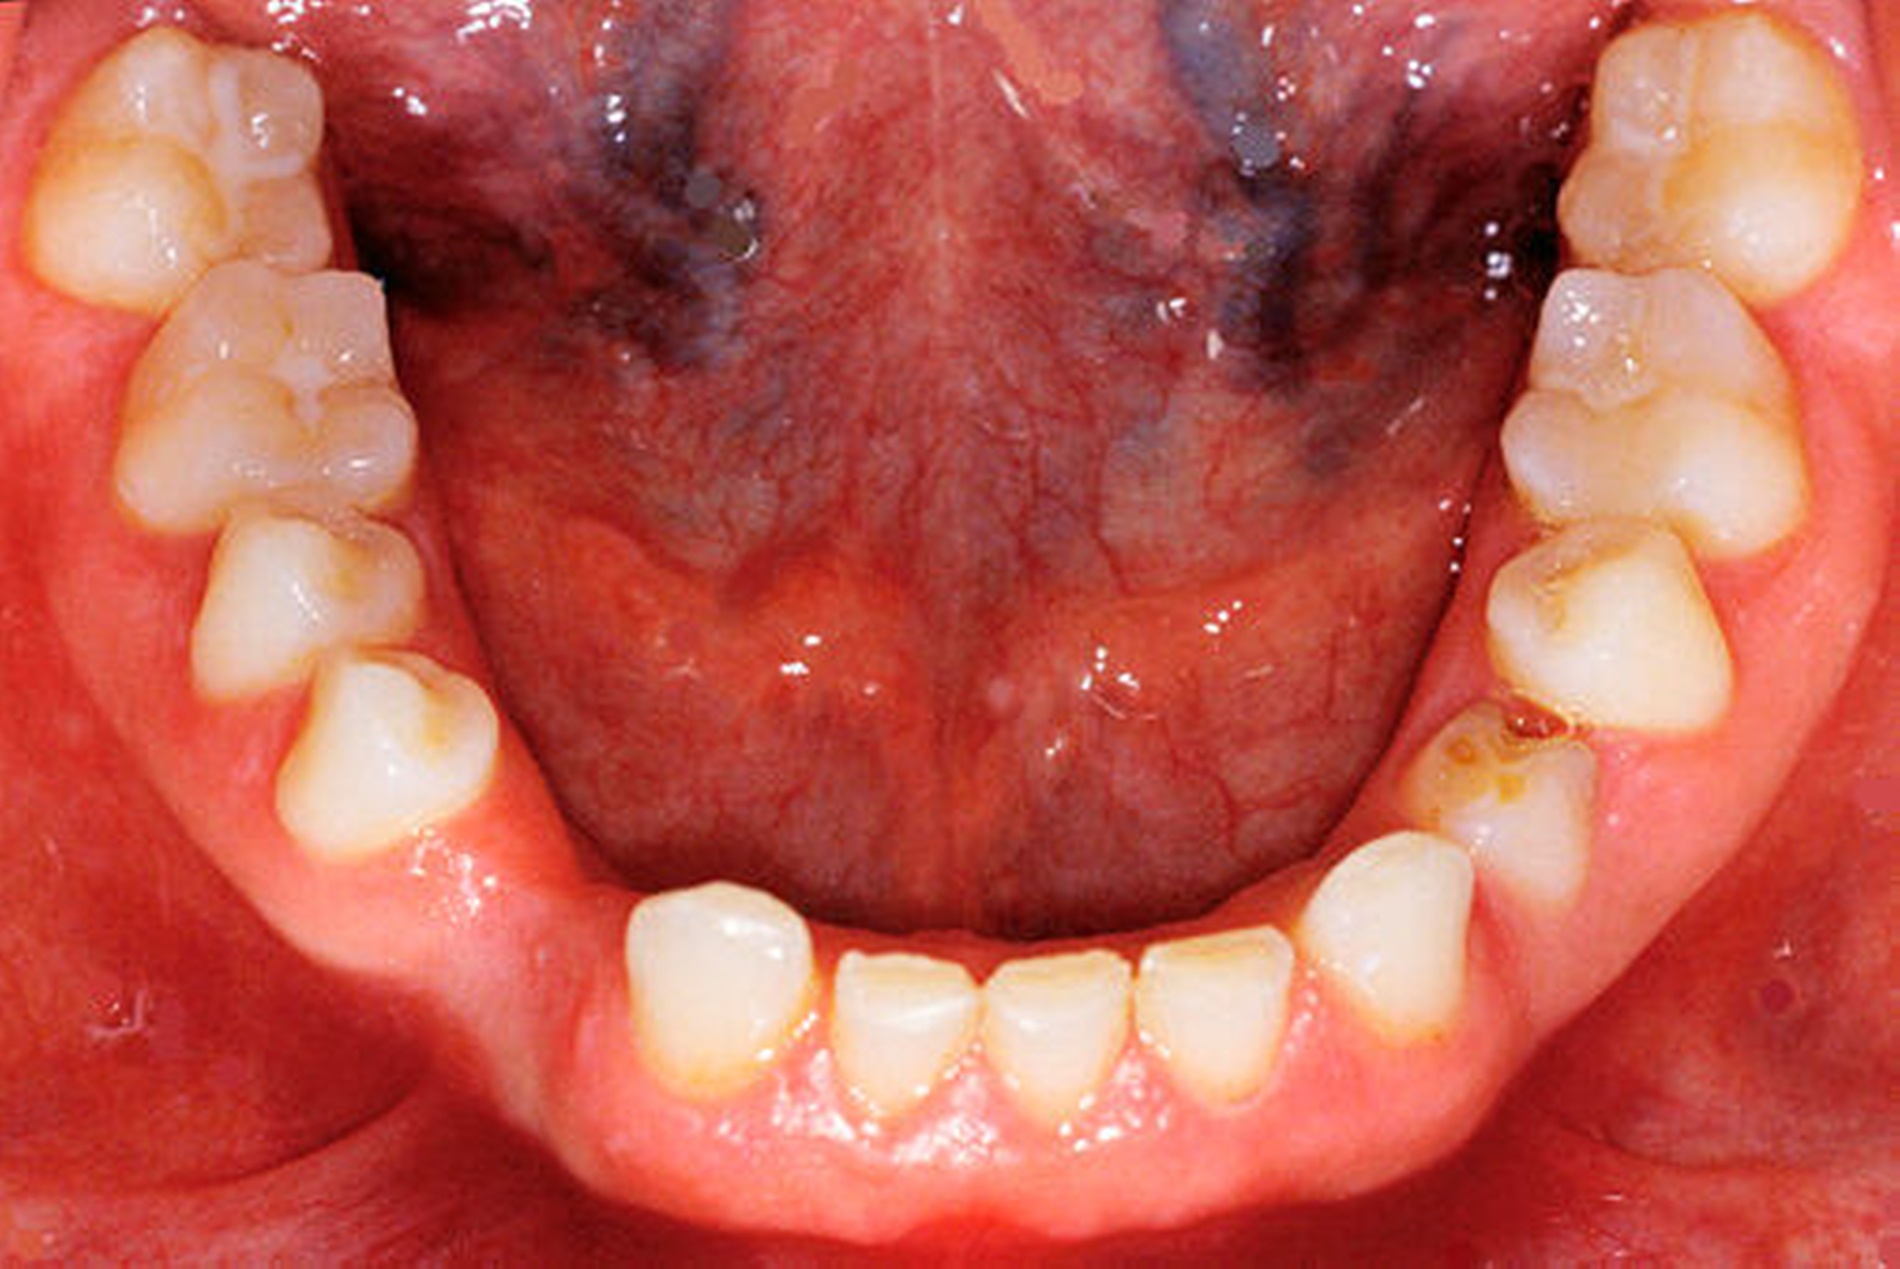

Die 16-jährige Patientin war unglücklich über ihre lückig stehenden Zähne und wünschte eine Verbesserung der durch die Dysgnathie beeinträchtigten Kaufunktion und ihres Aussehens (Porträtbilder en face und seitlich Abbildungen 1a und 1b, enorale Situation Abbildungen 2a bis 2c).

Anhand des klinischen Befunds, des Orthopantomogramms (Abbildung 3), der Durchzeichnung des seitlichen Fernröntgenbildes (Abbildung 4) und der Analyse der einartikulierten Modelle wurden folgende Diagnosen gestellt: skelettale und dentale Klasse II nach Angle (Distalbiss), Tiefbiss, Aplasie der Zähne 12, 14, 22, 34, 42, Persistenz und Infraposition der Zähne 54 und 74, Mikrodontie, starke Attrition der Oberkiefer- und der Unterkiefer-Front- und Eckzähne.